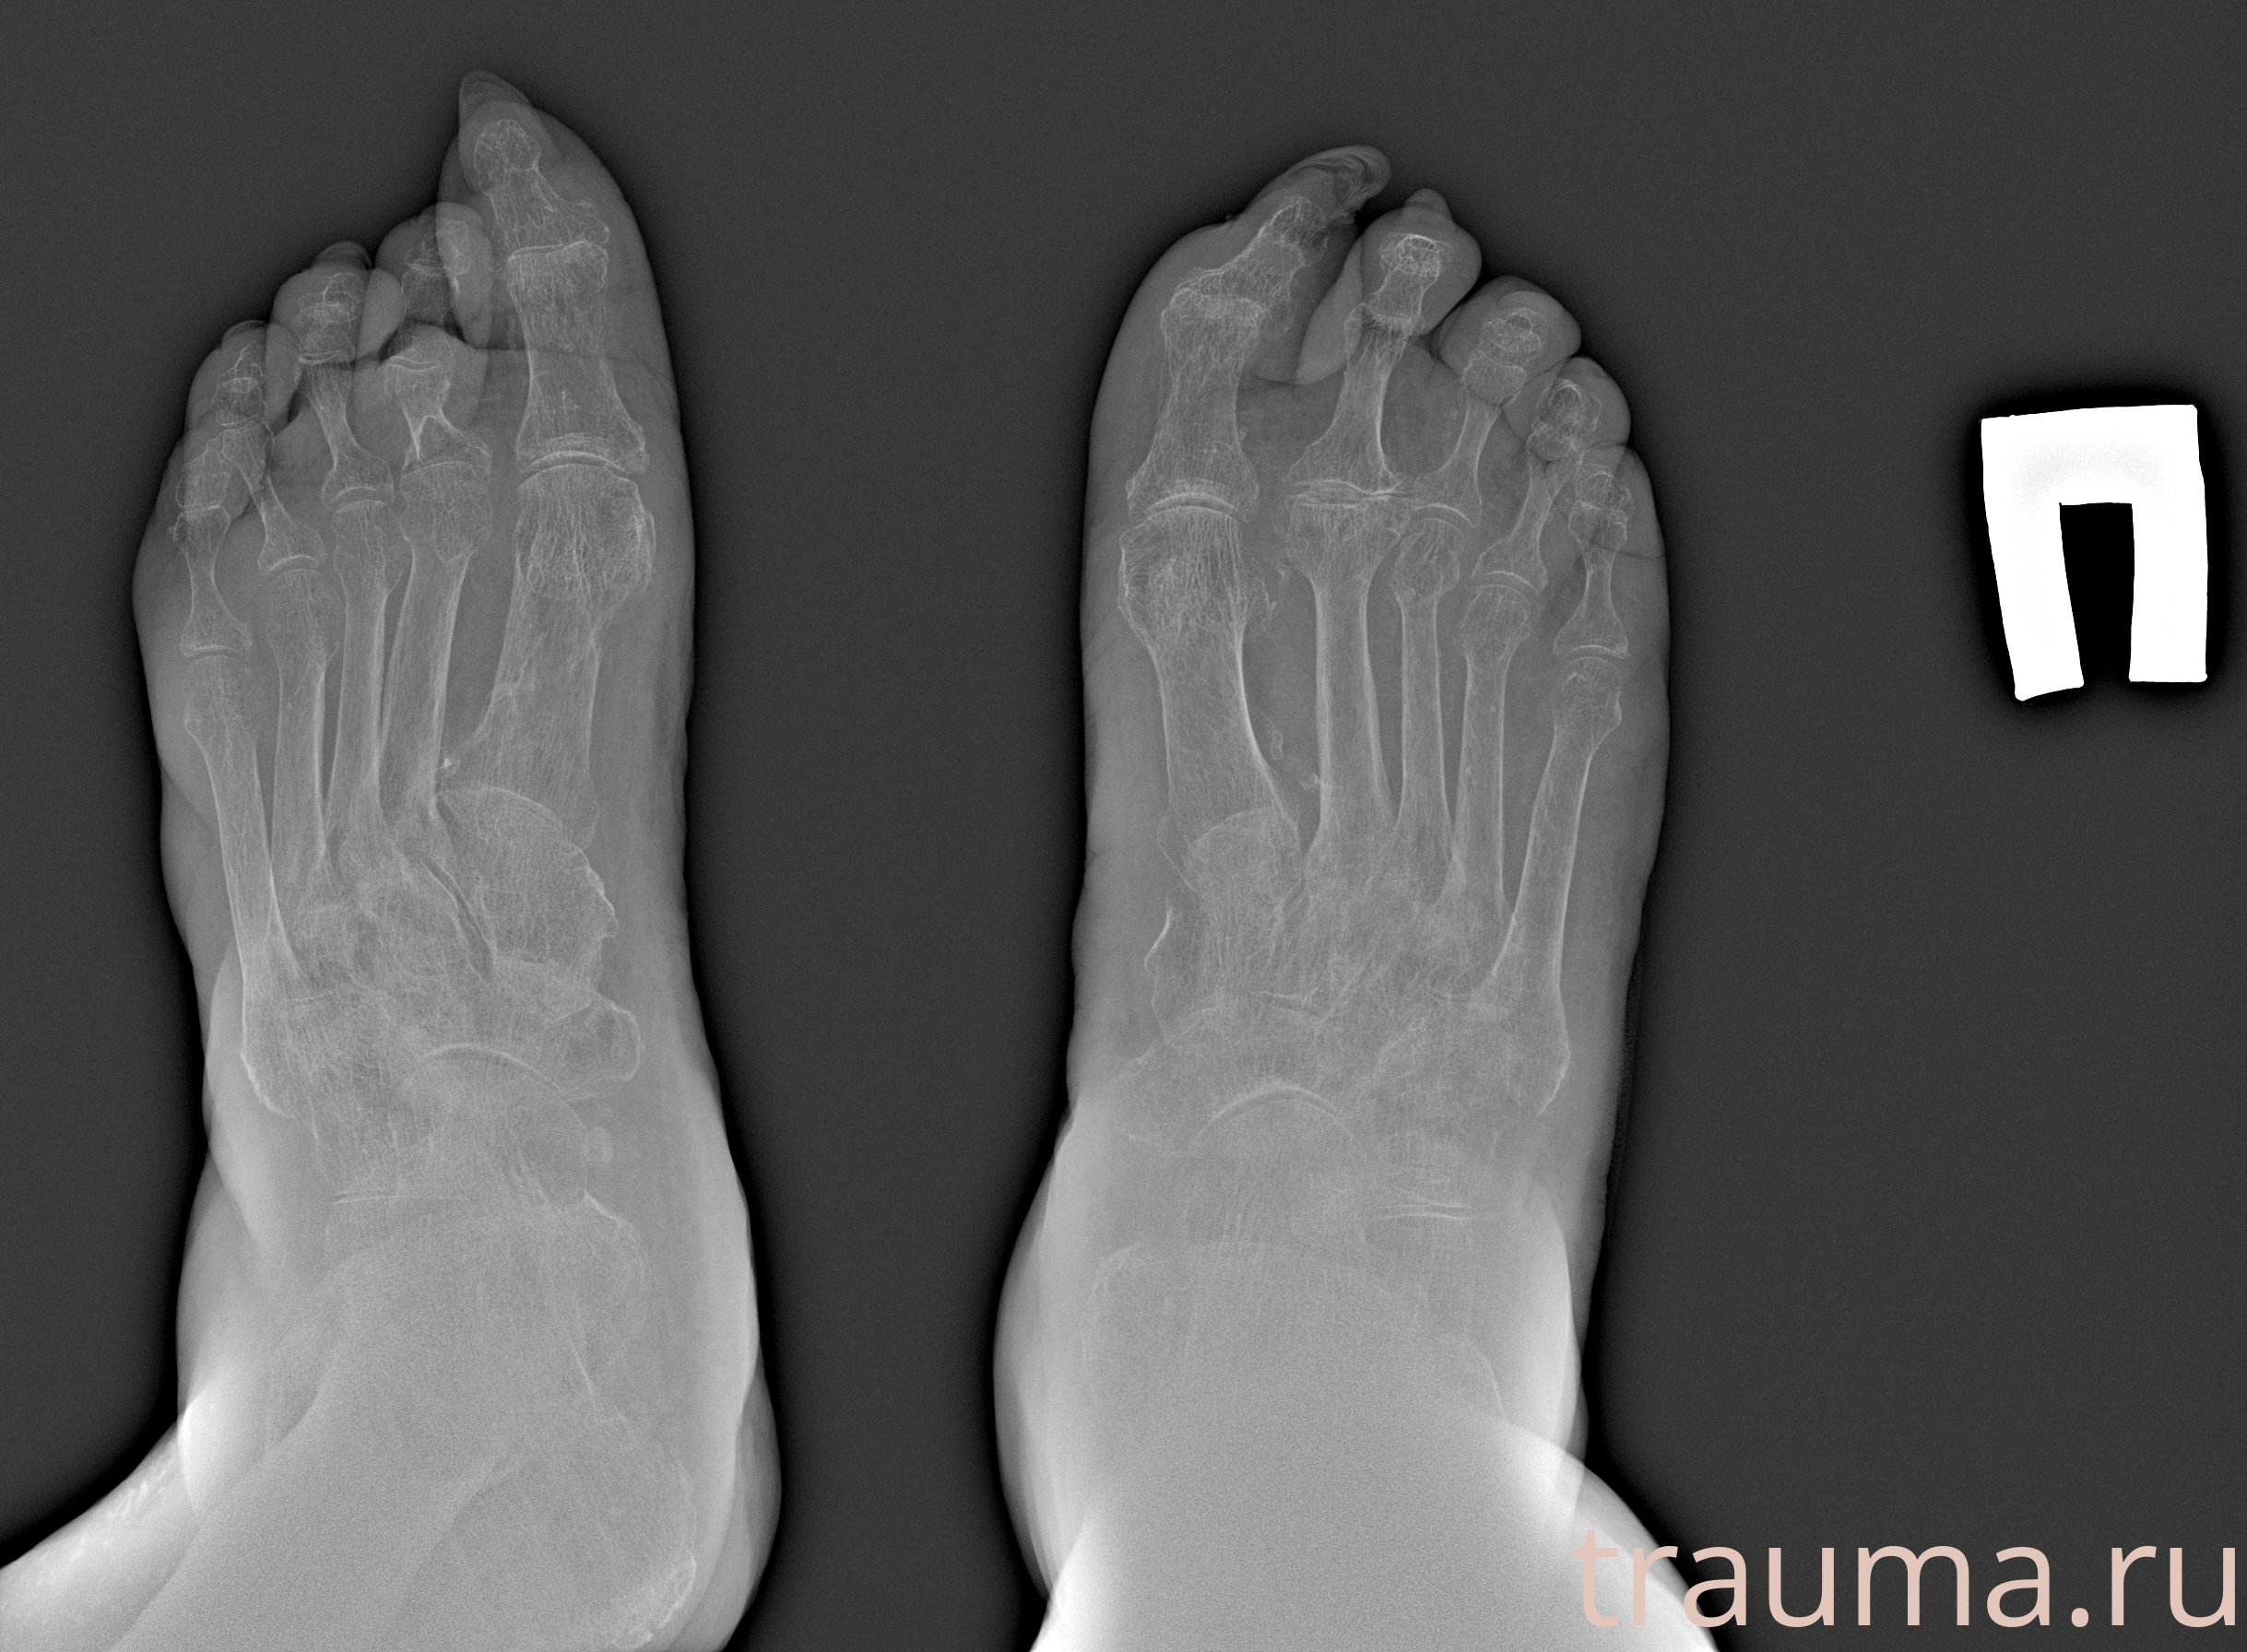

Рентгенограммы

Рентген на дому: по вашему адресу приезжает врач-рентгенолог, травматолог-ортопед с мобильным рентгеновским аппаратом, проводит диагностику травмы или заболевания, делает необходимые рентгенограммы, дает рекомендации по дальнейшему лечению. Получить качественные снимки в домашних условиях возможно благодаря уникальной методике, разработанной МосРентген Центром для института  Склифосовского